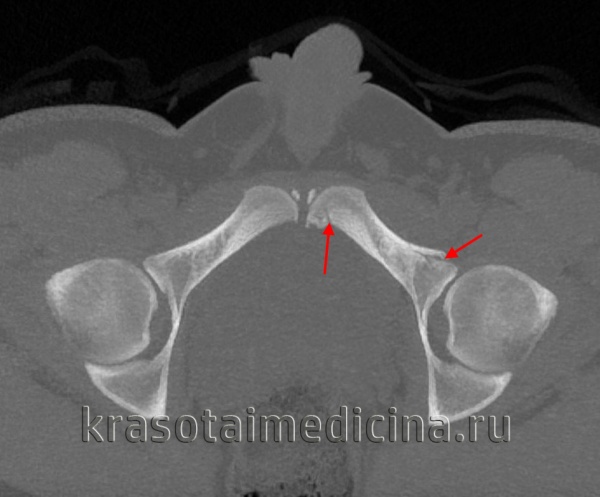

Для уточнения диагноза выполняют обзорную рентгенографию таза и рентгенографию поврежденного сустава в трех дополнительных проекциях. По возможности пациента направляют на КТ таза, поскольку эта методика позволяет более точно оценить тяжесть травмы и характер смещения отломков. Диагностическая ценность компьютерной томографии возрастает при повреждениях задней колонны и оскольчатых переломах.

Для исключения открытого перелома проводят вагинальное или ректальное исследование. Поскольку данная травма в 30% случаев сочетается с повреждением седалищного нерва, больным назначают консультацию невролога или нейрохирурга для точной оценки неврологического статуса.